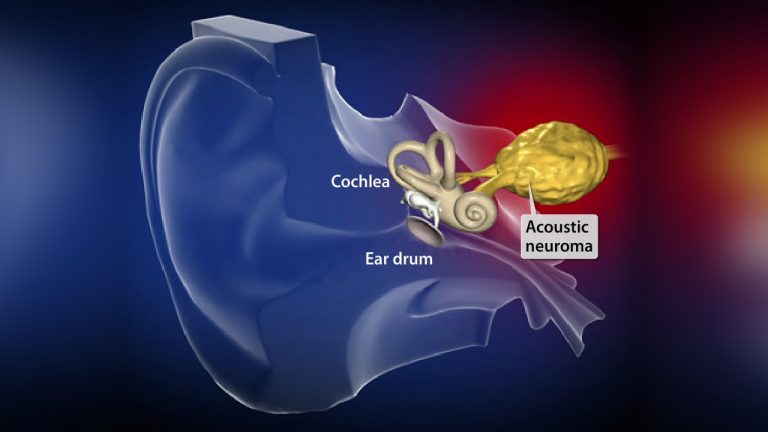

اغلب افراد هنگامی که دردی در ناحیه کمر و ستون فقرات خود حس میکنند، گمان میکنند که دچار بیماری دیسک کمر شدهاند. اما هر دردی در ناحیه کمر از علائم دیسک کمر به شمار نمیرود. ستون فقرات ما از مهرههایی تشکیل شده که بین هر دو مهره، ساختاری به...

بیماری فتق دیسک کمر که به صورت عامیانه به آن دیسک کمر گفته میشود عارضهای است که در اثر وارد شدن فشار زیاد به مهرههای کمر یا ضعیف شدن مفصلهای کمر در اثر عوامل مختلف حاصل میشود. اگر چه در بیشتر موارد، علائمی برای تشخیص دیسک کمر موجود است...